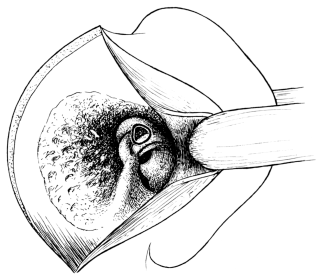

| 328. | The Caldwell-Luc Operation upon the Maxillary Sinus | 632 |

| 329. | Opening the Maxillary Sinus from the Nose | 633 |